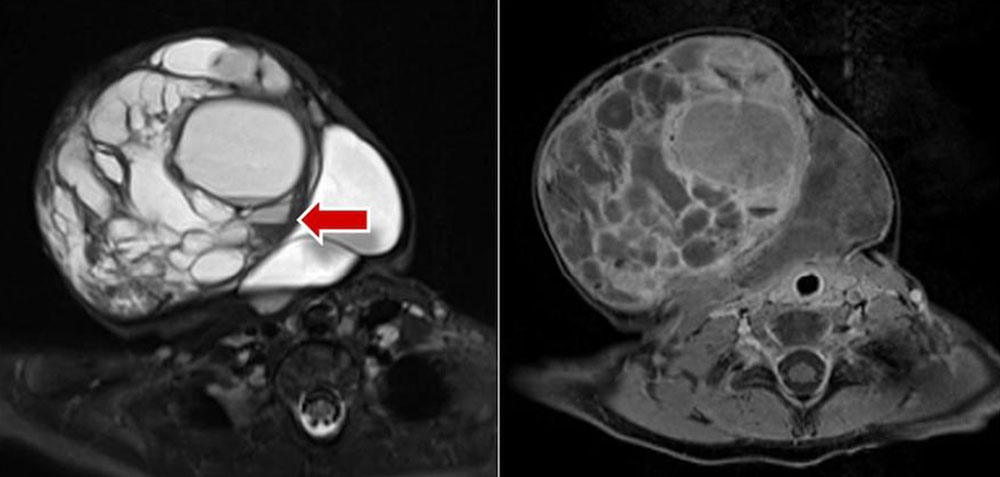

Venous malformation: In T2-weighted sequences, a strongly hyperintense signal predominates, which is highly visible on fat-suppressed T2-weighted sequences (STIR). Here they appear as septated, lobulated sponge-like or tubular masses, but often without any real space-occupying effect. Usually, venous malformations are isointense to the surrounding musculature on non-enhanced T1-weighted sequences. Spherical structures within the lesion with low signal on all sequences correspond to thrombi or calcified phleboliths which are pathognomonic for venous malformations when intralesional. Fluid-fluid levels can also be observed due to sedimentation phenomena within the venous malformations, but these are less frequent than in lymphatic malformations. After application of contrast medium, venous malformations slowly enhance contrast medium homogeneously. The average time to full contrast agent enhancement is about 90 seconds, which is significantly longer than for arteriovenous malformations (< 5 seconds). In contrast to arteriovenous malformations, in venous malformations the arteries supplying the affected extremity are not dilated. Flow voids are missing in venous malformations. Therapy-relevant venous connections (communicating veins) between the venous malformation and the deep venous system are occasionally identifiable on MRI. Abnormalities such as aplasia or hypoplasia of the deep and superficial venous system are also detectable.

13-year-old girl with severe cartilage damage in the knee joint due to extensive peri- and intra-articular venous malformation; therapy with surgical synovectomy and cartilage replacement